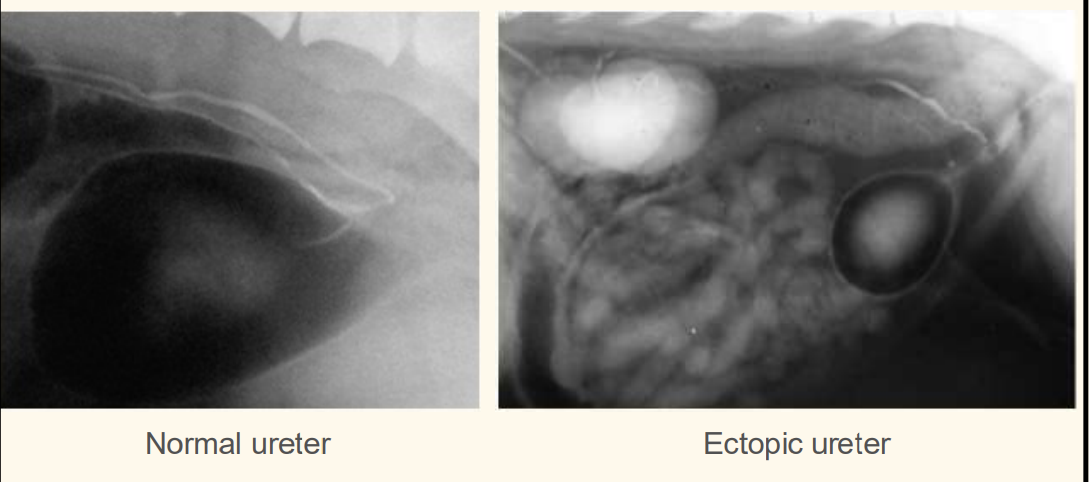

Contrast radiography – IV urogram with pneumocystogram

contrast radiography. what does this px have

air -ve contrast

whats wrong with this patient

ectopic ureter— hydroureter